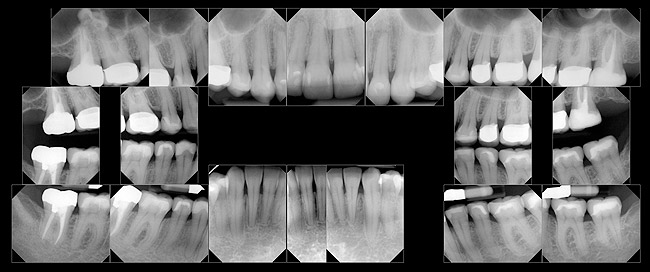

PARODONTAL: Evaluarea parodontală a evidenţiat adâncimi de sondare de 2-3mm în sextantele frontale şi de 2-5mm în cele posterioare. În regiunile laterale s-a observat o uşoară sângerare generalizată la sondare. Examinarea radiologică a obiectivat o pierdere osoasă orizontală generalizată uşoară spre moderată de 1-3mm. S-a descoperit un defect osos vertical pe faţa mezială a molarului 1.7. cu o adâncime de sondare asociată de 5mm (fig. 3). S-a stabilit un diagnostic parodontal de AAP tip II (parodontită uşoară).

Risc: redus

Prognostic: global bun, cu prognostic acceptabil specific molarului 1.7., datorită defectului său osos vertical mezial.

BIOMECANIC: Examinarea radiologică a identificat patologie apicală la nivelul molarilor 2.7. şi 1.7. (fig. 3, 4). Era vizibilă o leziune radiologică difuză, mixtă (fig. 4) apical de 1.6. şi 1.5., având un aspect care sugera un chist mucos de retenţie.1 Clinic, dinţii 2.7. şi 1.7. s-au dovedit a fi devitali la testare, în timp ce 1.5. şi 1.6. erau vitali.

S-au constatat carii dentare active la nivelul 1.7., 4.6. şi 4.4. Dinţii 1.7., 1.6., 2.4.-2.7., 4.4., 4.7. prezentau restaurări cu adaptare defectuoasă. Dinţii 1.7.-1.5., 2.5.-2.7., 3.5.-3.7., 4.5.-4.7. au fost notaţi cu structură compromisă datorită dimensiunii, tipului şi profunzimii restaurărilor. În plus, segmentul dentar 3.2.-4.2. prezenta semne precoce de eroziune chimică la nivelul muchiilor incizale. Corespunzător 1.6. s-a obiectivat o exostoză osoasă pe versantul vestibular (fig. 5), generând o înălţime scurtă a coroanei clinice şi un compromis restaurator ulterior.

Risc: crescut

Prognostic: slab; irecuperabil pentru dinţii cu carie dentară netratată.